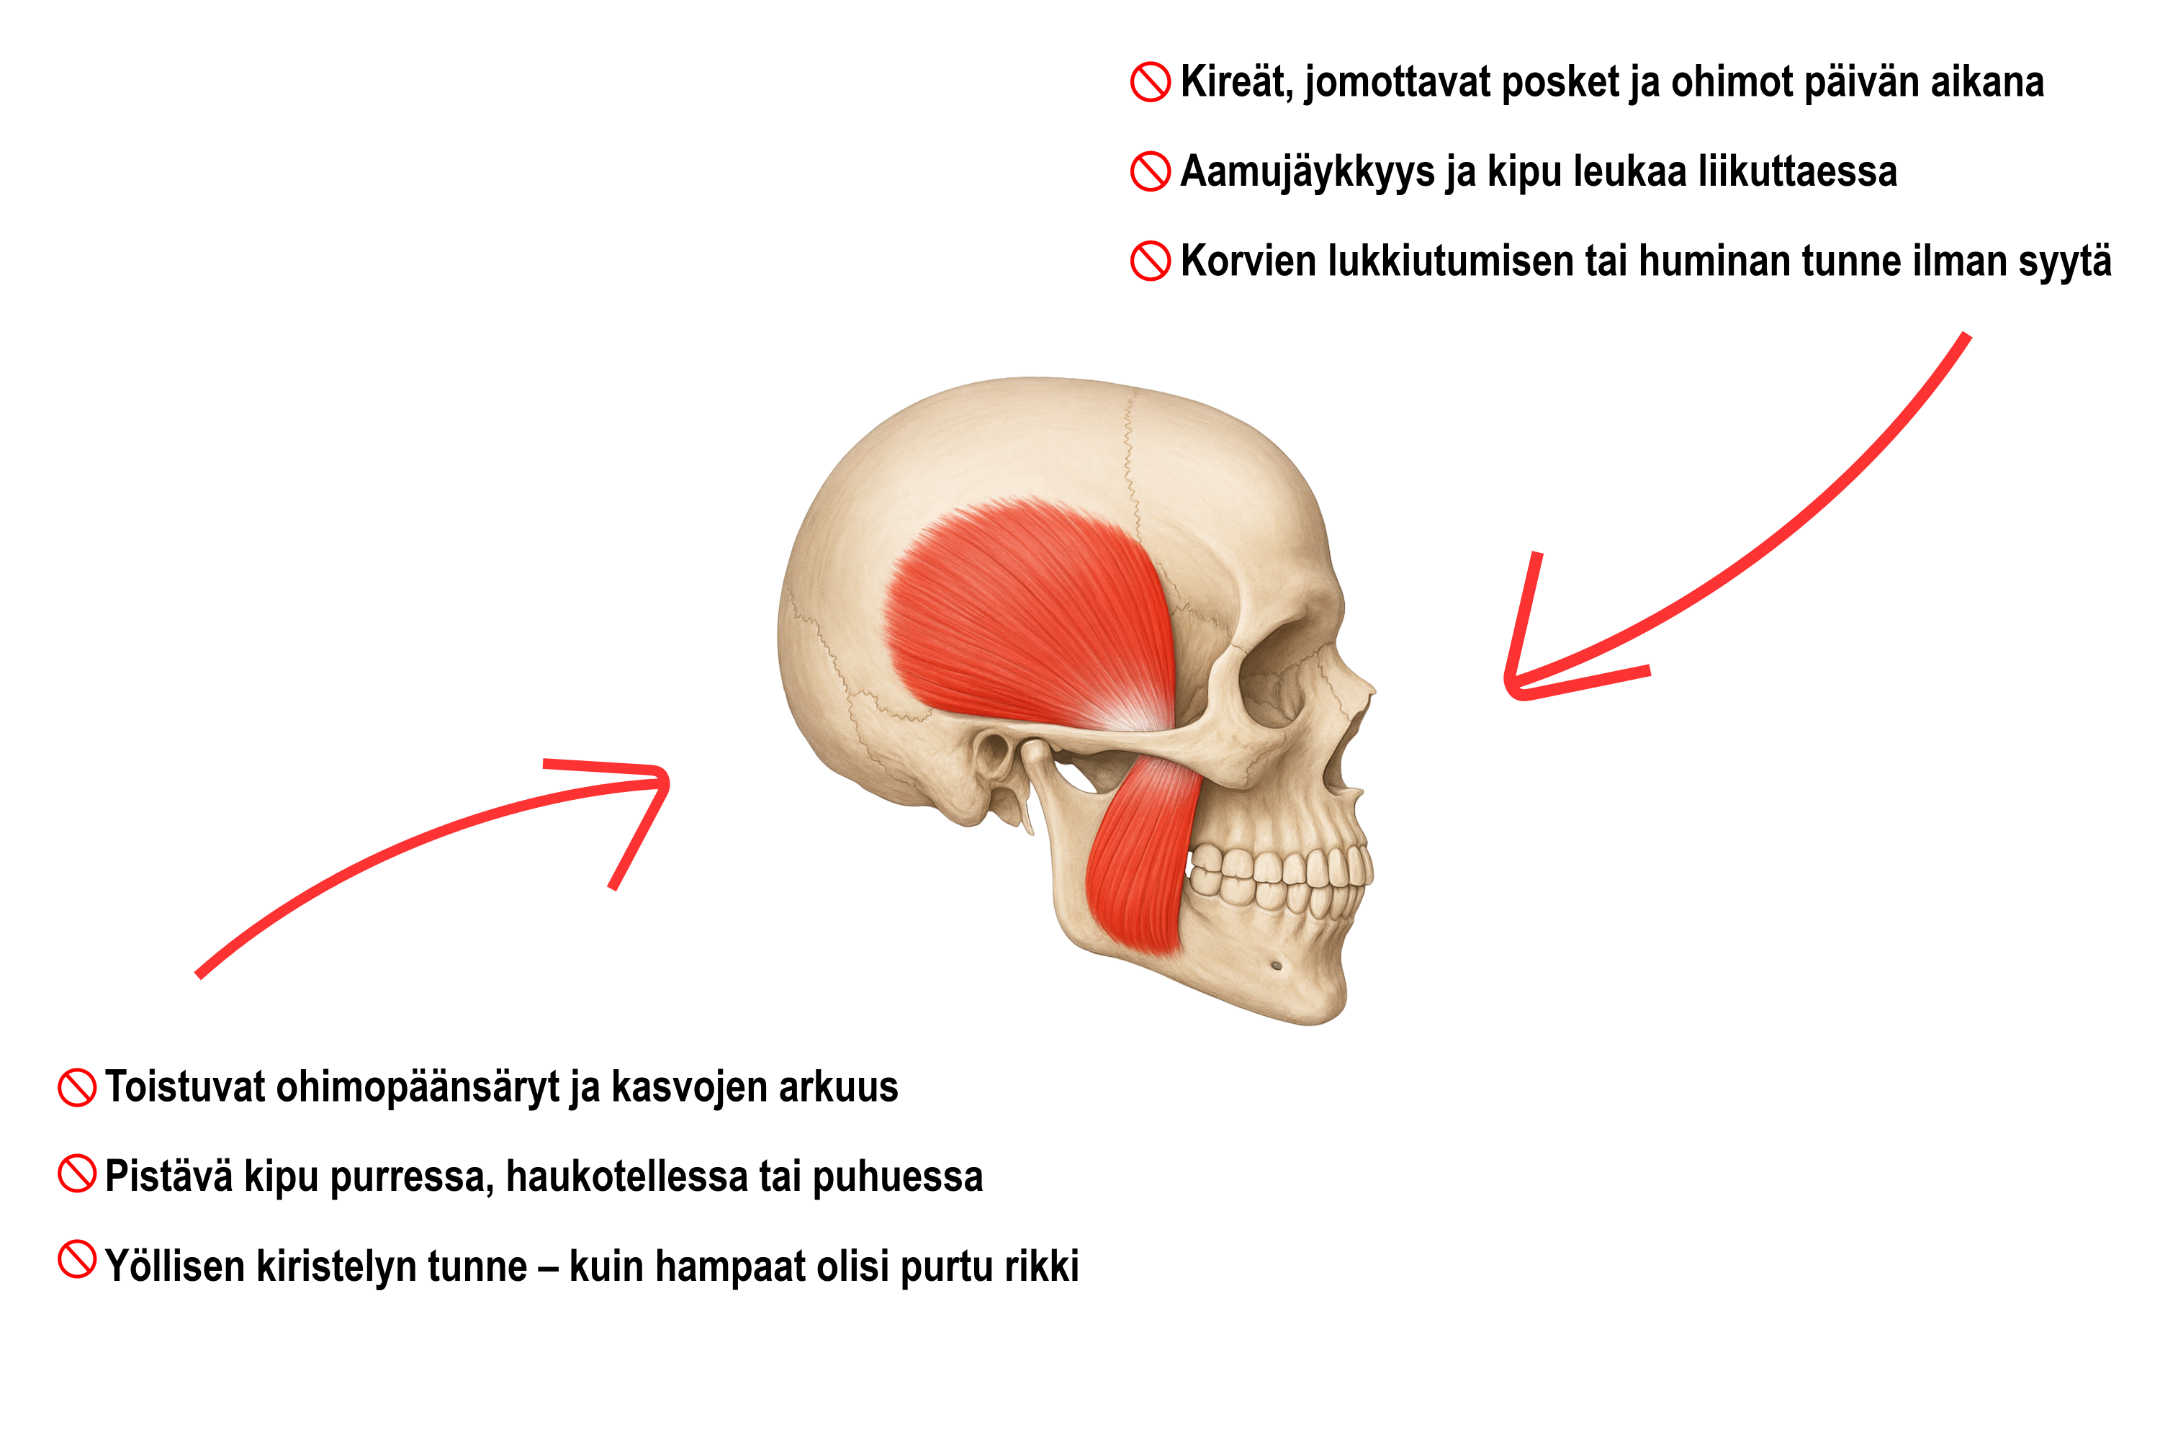

Tunnistatko itsesi näistä vaivoista?

✅ Leukaperien jatkuva jännitys alkaa hellittää, kun opetat lihaksille oikean tavan rentoutua.

✅ Vähentää yöllistä hampaiden kiristelyä ja puremisrasitusta opettamalla leualle oikeanlaisen lepomallin ja tuomalla lihaksiin joustoa.

✅ Päänsärkyjen ja ohimokivun määrä pienenee, kun kireät purentalihakset eivät enää rasita hermoja ja kudoksia.

✅ Purenta, syöminen ja puhuminen tuntuvat vaivattomilta — ilman repivää tunnetta tai nivelen ”jumiutumista”.